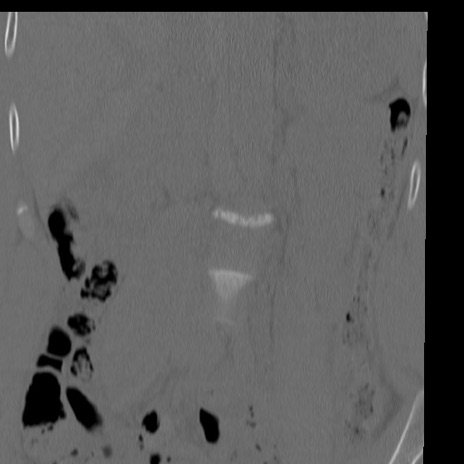

症例3 腰椎CT(冠状断像)

腰椎CT

矢状断像